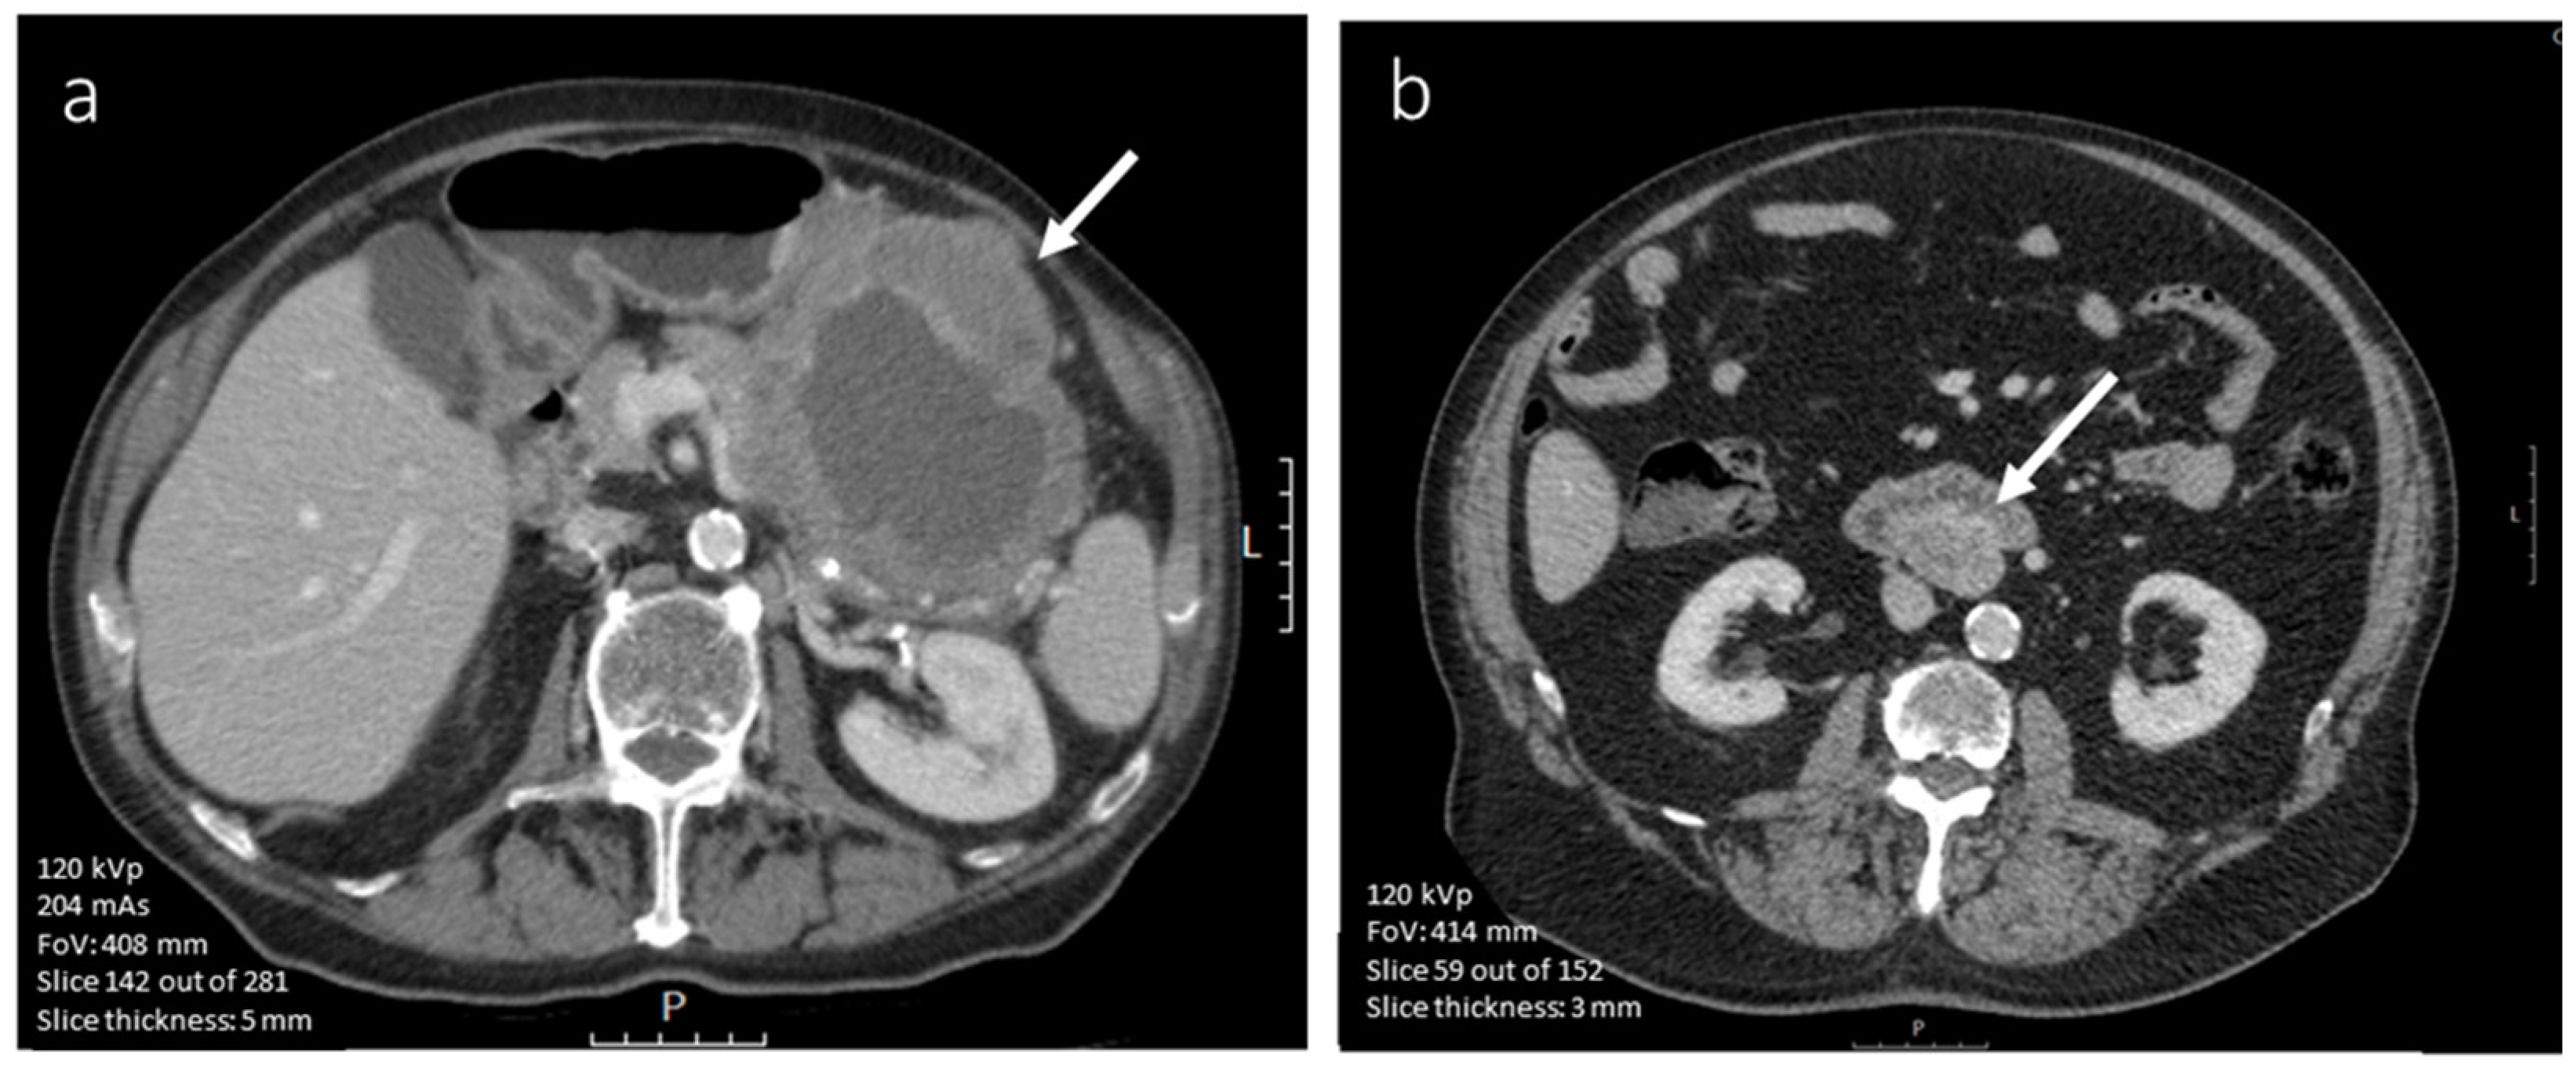

3.4.1. CE-CT Imaging